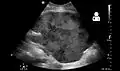

Imaging

Post operatively, kidneys are periodically assessed by ultrasound to assess for the imaging and physiologic changes that accompany transplant rejection. Imaging also allows evaluation of supportive structures such as the anastomosed transplant artery, vein, and ureter, to ensure they are stable in appearance.

- Postoperative bleeding following kidney transplant as seen on ultrasound[86]

Postoperative bleeding following kidney transplant as seen on ultrasound[86]